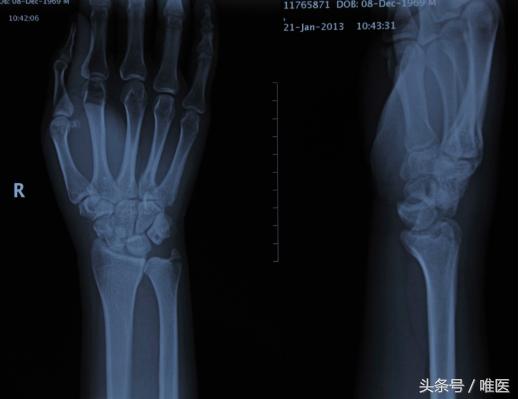

经舟骨月骨周围脱位,是指合并有舟骨骨折的月骨周围脱位,舟骨近端骨折块和月骨与桡骨远端关节面关系正常,而远端骨折块和其他腕骨一起发生脱位,可分为背侧脱位和掌侧脱位。

经舟骨月骨周围骨折脱位是腕部少见的严重损伤,占腕部损伤的3%-5%,多以背侧脱位为主,早期漏诊及误诊率极高,后期常发生舟骨骨不连、舟骨坏死、腕不稳定、创伤性关节炎等并发症,严重影响腕关节及手的功能,治疗上较为困难。对于经舟骨月骨周围脱位的治疗不仅要恢复腕关节正常的解剖结构,而且要确保舟骨骨折的愈合,避免发生舟骨坏死。

注:此图来源于网络